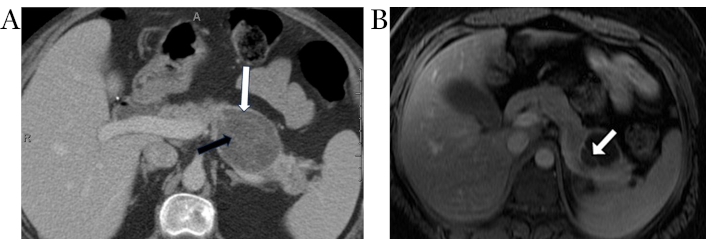

On CT, MCNs of the pancreas may appear as unilocular macrocysts that do not communicate with the pancreatic duct (Figure 3A). They are occasionally seen with peripheral eggshell calcification and mostly have heterogeneous cyst contents. The presence of thick, enhancing septations or mural nodules increases the likelihood of malignant transformation [50, 51].

Pancreatic mucinous cystic neoplasm. Axial contrast-enhanced CT image (A) demonstrates an ovoid hypodense cystic lesion in the pancreatic body/tail (white arrow) with thin internal enhancing septations (black arrow). Note the lack of upstream pancreatic ductal dilation. Axial post contrast T1-weighted MR image (B) in a different patient shows a cystic lesion in the pancreatic tail with a thin enhancing internal septation (white arrow)

Typical MRI features of MCN include a well-defined, unilocular, or oligolocular cyst. On T1-weighted images, MCNs may exhibit variable signal intensity, depending on the proteinaceous content of the cyst fluid (Figure 3B). On T2-weighted images, MCNs are hyperintense. Unlike IPMNs, the lesions do not show communication with pancreatic duct. MRI is superior to CT in identifying internal thick septations, mural nodularity, and any enhancing components. After gadolinium injection, enhancement of thick cyst wall is seen best on delayed phases of imaging owing to its fibrous nature [52].